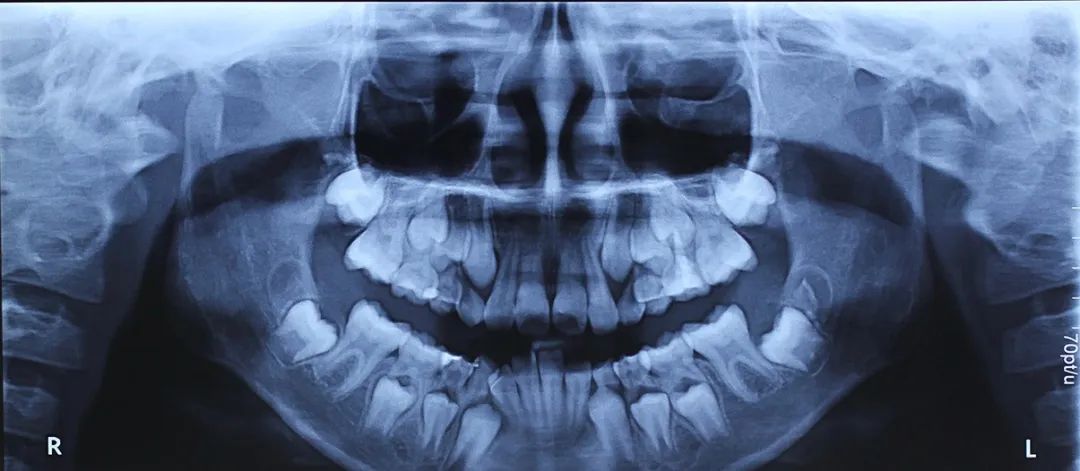

因此我们通过改变牙齿的位置,改变肌肉的力量,引导孩子自身的生长发育潜力,帮助孩子下颌尽最大可能生长好。我认为是在替牙的晚期,大概九岁或者十岁左右,这都算替牙晚期,在替牙晚期还没换完牙的时候,这个时候促进下颌骨生长会比较好。

当然每个孩子实际的身体的发育的年纪,跟岁数是不一样的,比如说我注意到有的孩子9岁就都换完牙了,有的孩子11岁还没换完牙,家长也可以以孩子上颌的2到2和下颌的2到2萌出后为参考,这也是早期矫正干预下颌后缩比较好的时期。

上下2-2萌出